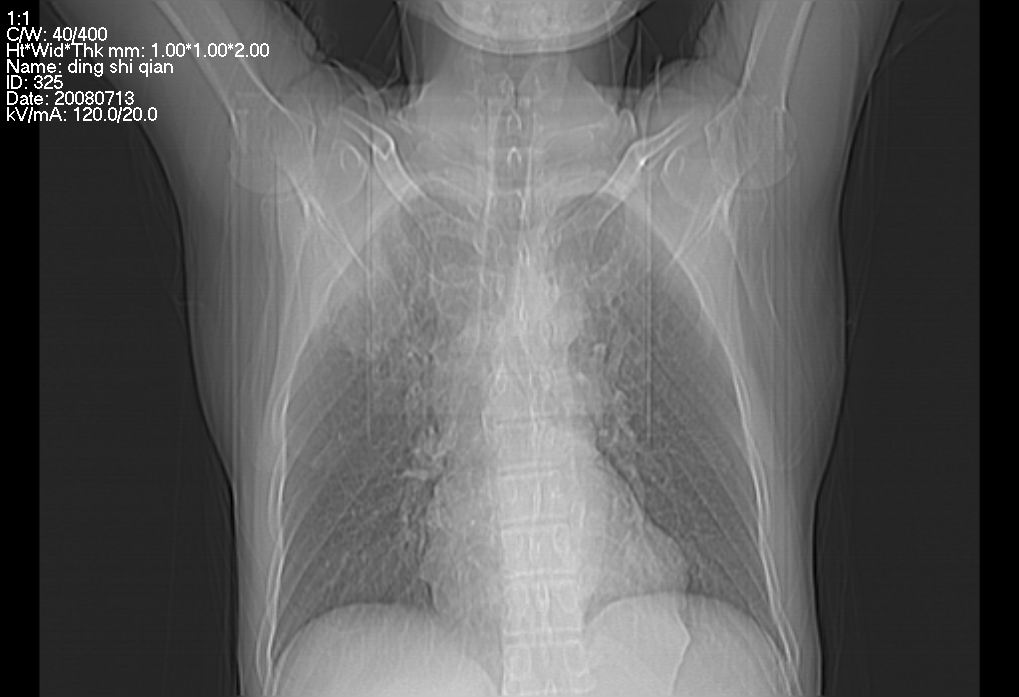

标题: CT14654:男 50岁 近来胸痛 [打印本页]

标题: CT14654:男 50岁 近来胸痛

右侧上肺块状软组织影,浅分叶,边缘毛刺证,与胸膜粘连,考虑:周围性肺癌

首先考虑周围性肺癌,建议强化或穿刺明确